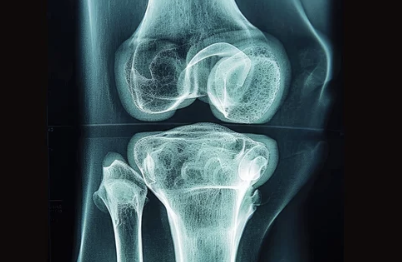

무릎 연골 손상이 의심된다면 병원을 방문하여 정확한 진단을 받는 것이 중요해요. 의사는 환자의 증상과 병력을 듣고, 신체 검진 및 영상 검사를 통해 연골 손상 여부를 확인합니다.

- X-ray: 뼈의 상태를 확인하고 관절염 여부를 판단하는 데 도움이 됩니다.

- MRI: 연골, 인대, 힘줄 등 연부 조직의 손상 여부를 정확하게 확인할 수 있습니다.

- 관절경 검사: 관절 내부를 직접 확인하고 필요한 경우 치료까지 동시에 진행할 수 있습니다.